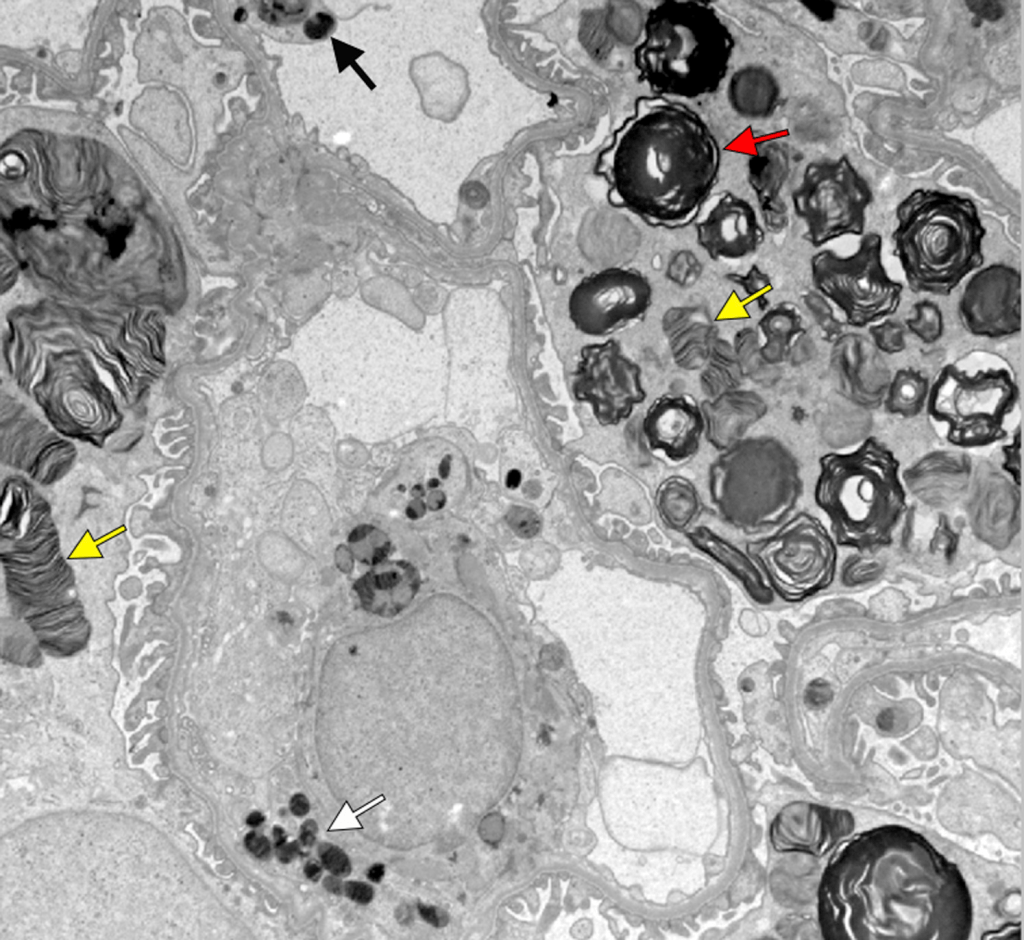

From a nephrology perspective, Fabry disease carries major clinical significance. Kidney involvement typically begins with proteinuria and progresses to CKD and kidney failure in untreated patients. Histologically, characteristic “zebra bodies” – concentric lamellar inclusions seen on electron microscopy (see figure below) – reflect Gb3 deposition in podocytes, peritubular capillary endothelial cells, and other kidney cells. Importantly, by the time kidney manifestations appear, patients almost always have extra-kidney disease, which means that a nephrologist who makes the diagnosis can significantly influence the patient’s overall trajectory. In advanced disease, cardiomyopathy, stroke, neuropathy, and dermatologic complications are common, with cardiac events representing the leading cause of death. Furthermore, patients can experience severe debilitating pain, irritable bowel syndrome-like symptoms, and anhidrosis, which also cause significant morbidity. Finally, there is always the opportunity to screen the patient’s family and initiate treatment early in those affected to prevent loss of kidney function and other manifestations of the disease.

Fabry nephropathy with typical Fabry glycosphingolipid inclusions shaped as multilamellated myelin figures (red arrow) and zebra bodies (yellow arrows) in podocytes. There are also smaller inclusions in endothelial cells (black arrow) and mesangial cells (white arrow; electron microscopy).